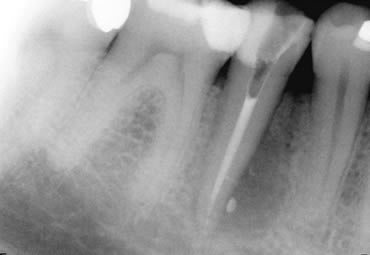

Large Perio-endo lesion, before treatment, during treatment and at 18 month follow up